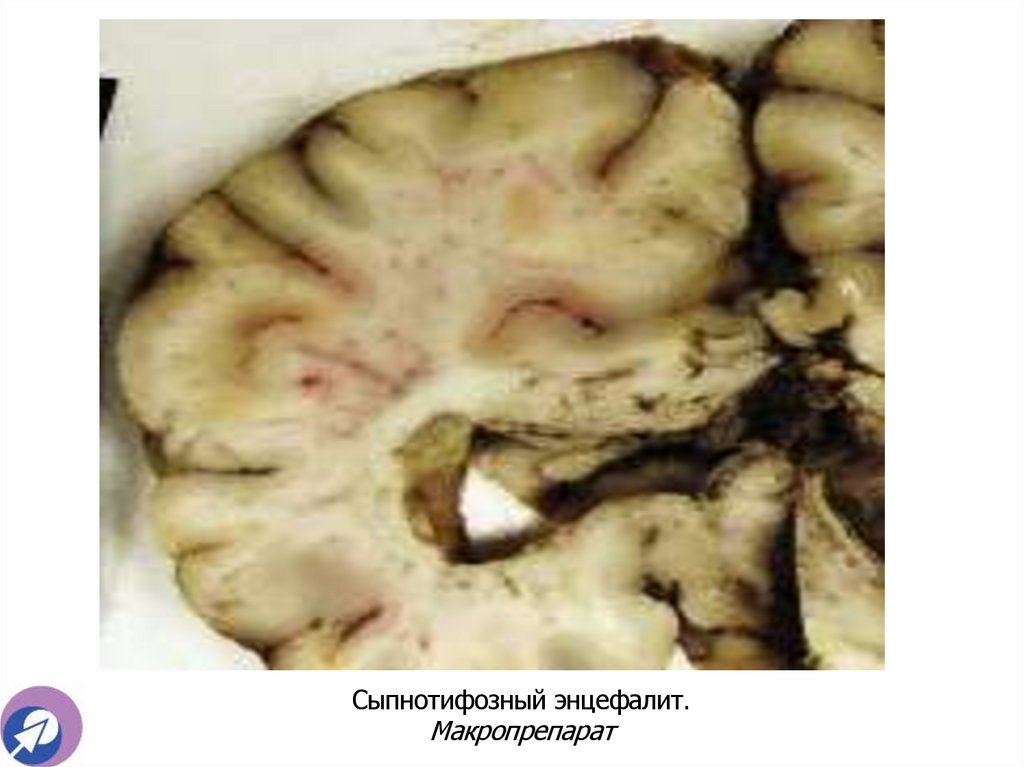

Сыпнотифозный энцефалит. Макропрепарат

Сыпнотифозный энцефалит. Макропрепарат. Демонстрация

19. Сыпнотифозный энцефалит. Макропрепарат